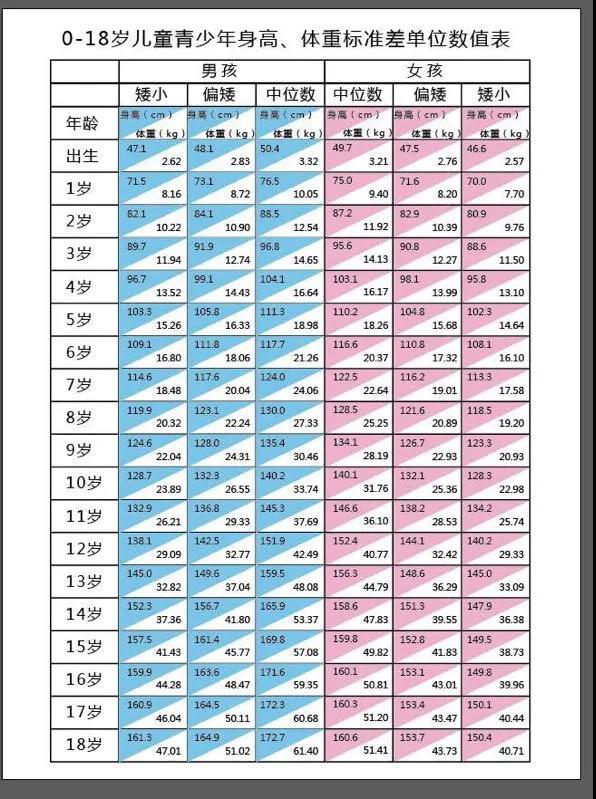

矮小、性早熟门诊持续为身高没有达标准和过早发育的儿童提供身高、发育评估,指导家长做好孩子的身高科学管理。对照下表,看您家孩子属于个子矮小型吗?